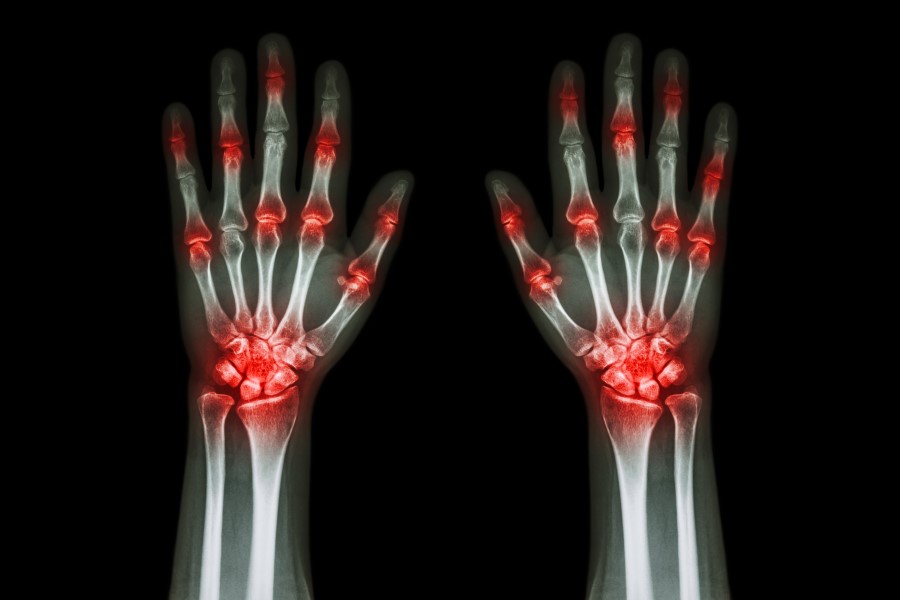

Reumatoidalne zapalenie stawów (RZS) jest zaliczane do przewlekłych chorób układu tkanki łącznej o podłożu immunologicznym. RZS charakteryzuje się nieswoistym zapaleniem symetrycznych stawów oraz występowaniem zmian pozastawowych i powikłań układowych, które mogą prowadzić do niepełnosprawności, inwalidztwa i przedwczesnej śmierci. Jak wspomóc leczenie RZS dietą? Jakich produktów unikać przy tym schorzeniu?

Choroba typowo atakuje te same miejsca po obu stronach ciała. Początkowo są to drobne stawy rąk i stóp, a w miarę postępu choroby wiele innych stawów. Charakterystycznymi objawami reumatoidalnego zapalenia stawowów są: